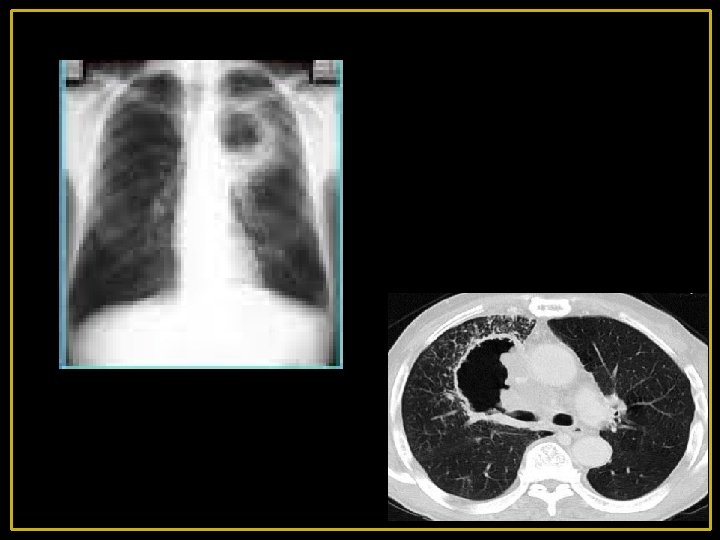

2 - malignes: Le cancer broncho-pulmonaire excavé: - Excavation dans 1/6 des cas environ (++ épidermoïde) - Peut se voir dans les tumeurs centrales ou périphériques - Elle peut contenir un niveau hydro-aérique - La paroi cavitaire est généralement épaisse et de contours irréguliers - Une image en « grelot » est possible par détachement d'un fragment de tissu nécrosé